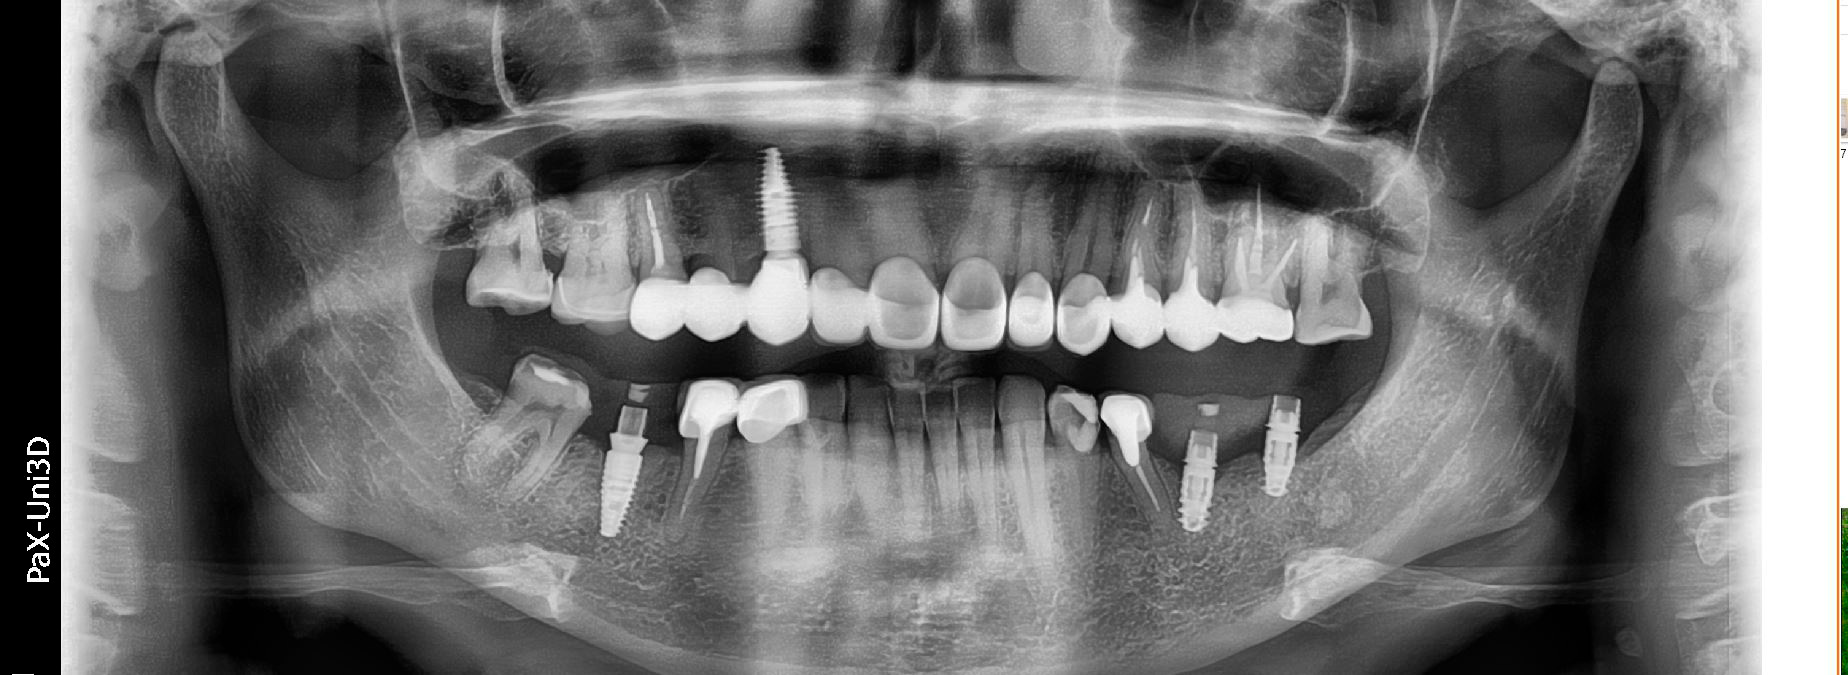

Лесі порекомендував звернутись до мене її лікуючий стоматолог з приводу корекції естетики усмішки. Після планування та обговорення всіх деталей ми встановили імплантант в естетичній зоні. Згодом змоделювали індивідуальну форму та обрали пропорції нових керамічних вінірів.